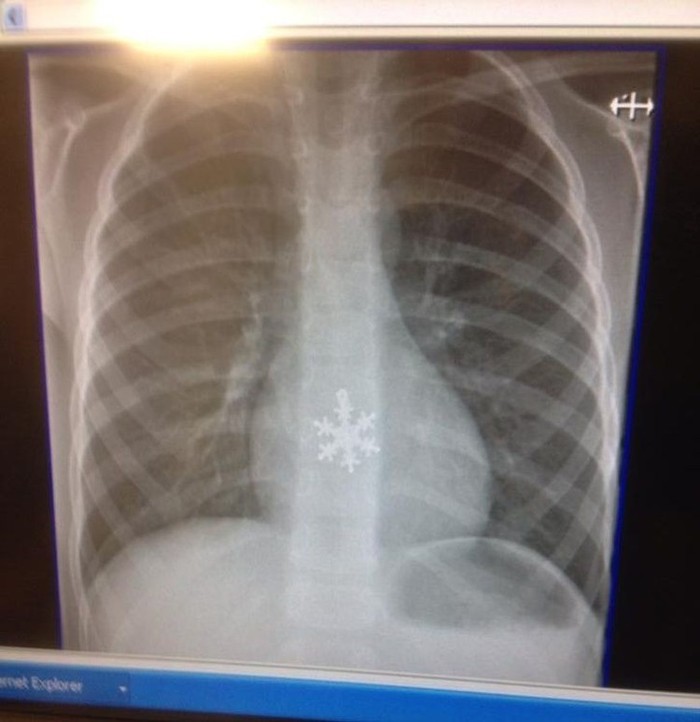

Menelan kepingan salju. (Foto: Brightside)